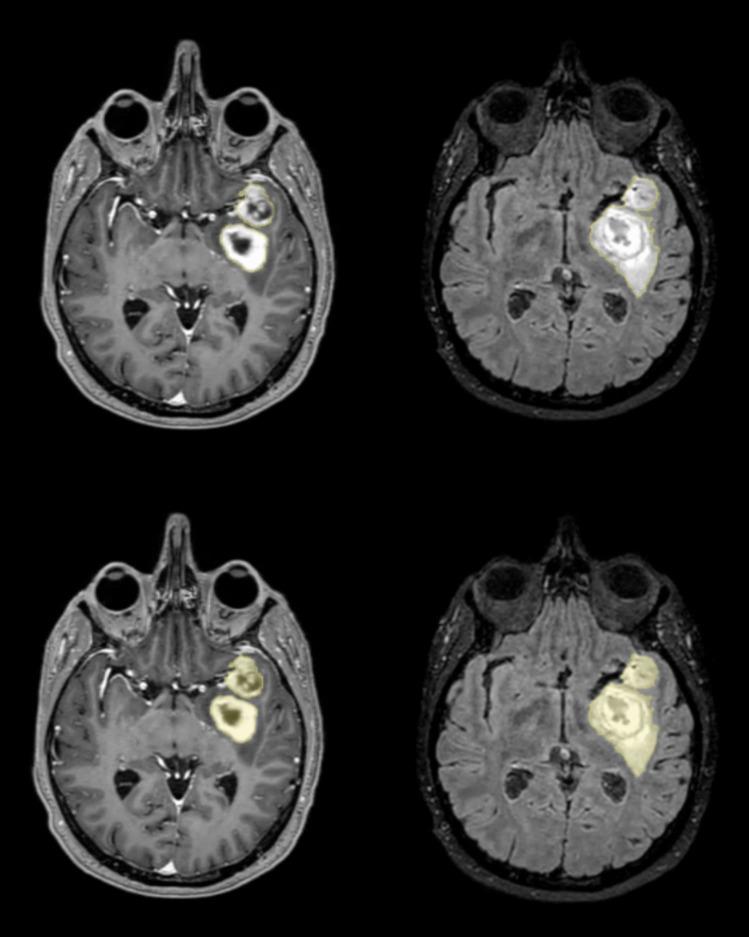

Fifteen newly diagnosed GBM patients were treated for 7 days preoperatively with AF in addition to standard of care (SOC) treatment with corticosteroids. The change in edema volume was assessed volumetrically using T2/FLAIR weighted MRI and compared to a control group of 10 GBM patients receiving SOC only.

15例新诊断的GBM患者在术前除接受皮质类固醇标准治疗(SOC)外,还接受了7天的AF治疗。使用T2/FLAIR加权MRI对水肿体积变化进行体积评估,并与仅接受SOC治疗的10例GBM患者对照组进行比较。